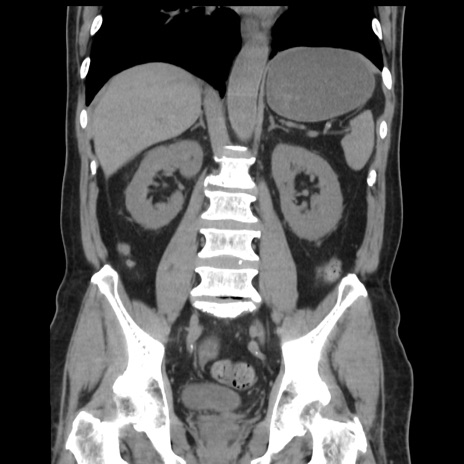

症例16(冠状断像)

【症例】 70歳代男性

【主訴】 腹痛、嘔吐

【現病歴】 約1ヶ月前より間欠的に腹痛と嘔吐あり、当院消化器内科を受診したところCTで多発する肝臓のLDAを指摘され、精査中であった。以降は消化器症状は安定していたが、2日前より嘔気と腹痛があり、同日より排便・排ガスが消失した。改善認めず、 本日、救急外来を受診した。

【既往歴】 大腸ポリープ切除後。

【身体所見】意識清明・会話良好、BT 36.3℃、BP 127/80mmHg、 P 80bpm、腹部:膨満あり、平坦・軟、上腹部正中および下腹部正中に圧痛あり、反跳痛なし、筋性防御なし。

【データ】WBC 7200、CRP 0.77